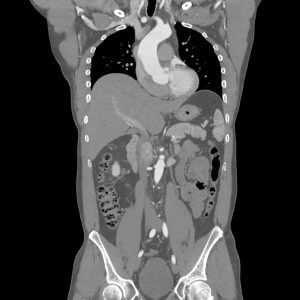

МСКТ брюшной полости и забрюшинного пространства - современный метод диагностики, который обеспечивает высокую степень детализации и делает визуализацию внутренних органов максимально удобной. Мультиспиральная компьютерная томография (так расшифровывается аббревиатура МСКТ) основана на использовании рентгеновского излучения. Ткани, имеющие различную плотность, по-разному пропускают рентгеновские лучи. Эта информация считывается с помощью специального оборудования - томографа. Мультиспиральные томографы, используемые в «Семейном докторе» позволяют получать 64 среза толщиной 0,625 мм. за один оборот гентри (рабочей части томографа). Эта информация обрабатывается с помощью мощного компьютерного обеспечения, реконструирующего изображения интересующей области в любой плоскости, а также в 3D (объемное изображение). МСКТ-исследование брюшной полости и забрюшинного пространства активно используется для оценки состояния органов, относящихся к этой области, дифференциальной диагностики и выявлении заболеваний на ранних стадиях.

КТ органов брюшной полости даёт изображение каждого органа в разрезе, при этом картинка не накладывается одна на другую. Компьютерная томограмма показывает наличие заболеваний желудочно-кишечного тракта и забрюшинного пространства, таких как: раковые опухоли, камни, инородные тела, травмы, кистозные образования.

Компьютерная томография органов брюшной полости - прогрессивный метод обследования внутренних органов и забрюшинного пространства, который позволяет получить послойные снимки структур тканей. Он отличается высокой точностью, безболезненностью и информативностью результатов. В результате проведения КТ, можно обнаружить первичные и вторичные объёмные образования, абсцессы, поражения забрюшинных узлов, травмы и аневризмы, распространение метастазов. Ценность полученной информации заключается в том, что с её помощью можно выявить патологии на самых ранних стадиях, разработать стратегию лечения, следить за эффективностью его проведения.

Компьютерная томография (КТ) - это универсальный метод диагностики, который заключается в получении снимков и, на основе их построения, 3D-изображений отдельных внутренних органов. Исследование брюшной полости и забрюшинного пространства (второе название - ретроперитонеальное пространство) проводится с минимальным шагом от 0,5 миллиметра. Томограф сканирует не только внутренние органы, но и сосуды, лимфоузлы. Затем компьютер анализирует полученную информацию и выстраивает высокоточные снимки обследуемых участков.

Компьютерная томография ретроперитонеального пространства определяет: наличие камней в желчных протоках и почках; врожденные аномалии; абсцессы; атеросклероз; сосудистые изменения; новообразования и инородные тела; поражение лимфоузлов; травмы; кровоизлияния; опухоли и кисты.